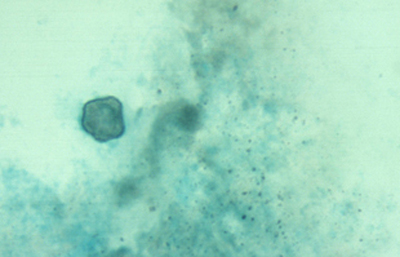

Las coloraciones empleadas en extendidos corneales para visualizar los quistes y trofozoitos de Acanthamoebas usando métodos sencillos son múltiples, siendo las que nos parecen más recomendables las coloraciones de Giemsa y el Acido Periódico de Schiff (PAS), (Figura 33 y 34) ambas usuales en los laboratorios de patología.

Fig. 33 PAS, Original x250

Fig. 34 PAS, Original x160

En nuestra práctica empleamos usualmente el Contraste de Fases, el Blanco de Calcofluor, la coloración de Giemsa, y frecuentemente la de PAS. Las tres primeras son más sencillas y rápidas y pueden practicarse en un mismo extendido. Estas técnicas y coloraciones son las mismas que empleamos para el estudio de extendidos en queratitis micóticas.